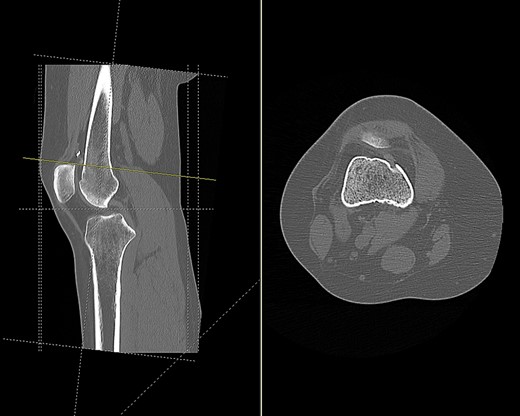

CT scan of the right knee showing perforation of anterior femoral cortex (sagittal and axial view).

Based on tunnel positions, we conclude that the original surgeon had perforated the anterior femoral cortex when drilling from the medial femoral condyle. Due to this an anterior cortex endobutton fixation was used to supplement the medial condylar interference screw fixation. A degree of likely soft tissue interposition in the suprapatellar region led to migration of the endobutton, and subsequent rupture from its scar tissue bed following minimal trauma.